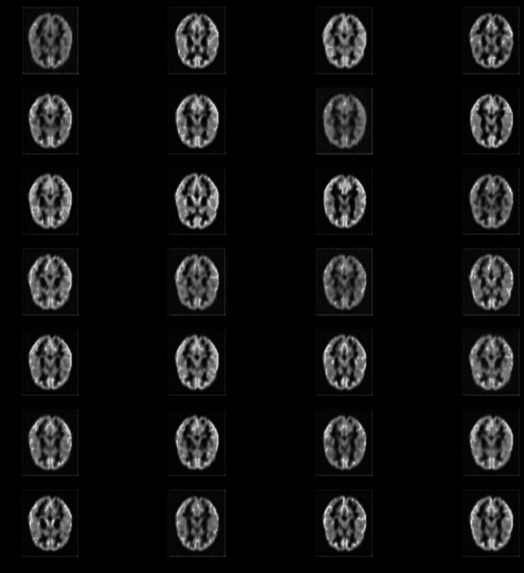

One of the main aspects of our project is MRI Image Synthesis. In this, we convert T1-Weighted images into T2-Weighted images. Along with this, our other model helps by generating Segmented Brain MRI images to show the distribution of white matter.

So we have created two models, one for Image synthesis and the other does Segmentation. Both works on generating images. We have implemented VAEs to achieve the purpose.